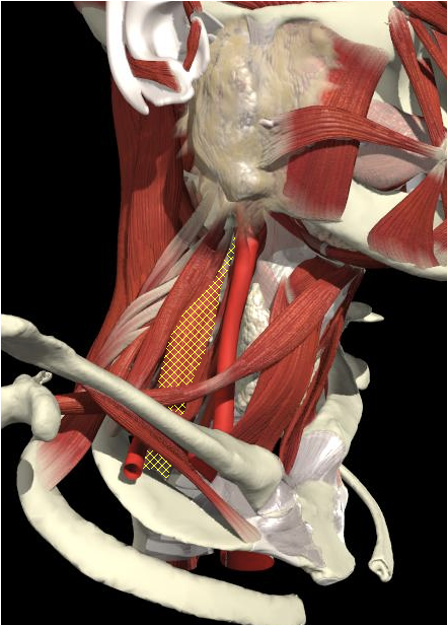

Structures to Avoid

Brachial Plexus

The BP lies inferior to a line from the posterior margin of the sternomastoid at the level of the cricoid cartilage to the midpoint of the clavicle

The BP lies inferior to a line from the posterior margin of the sternomastoid at the level of the cricoid cartilage to the midpoint of the clavicle. Scalenus medius is behind and above line.

Interscalene Groove & Brachial Plexus

Interscalene groove